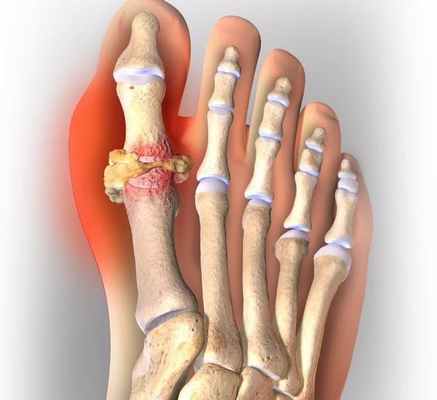

Причинами появления подагры принято считать факторы, которые приводят либо к снижению выделения мочевой кислоты с мочой, либо к ее повышенной продукции в организме, либо сочетание тех и других. В результате повышения концентрации мочевой кислоты в крови происходит отложение ее кристаллов в суставных и/или околосуставных тканях, почках и других органах в виде своеобразных гранулем – тофусов (лат. tofus — пористый камень). Отложение кристаллов вызывает воспалительные явления. Чаще всего болезнь поражает большие пальцы ног, стопы, лодыжки, колени, пальцы рук, запястья и локти, однако может затрагивать любой сустав.

Наиболее распространенным проявлением подагры является острый моноартрит, характеризующийся внезапной сильной болью и отеком. Однако могут поражаться сразу несколько суставов – обычно первый плюснефаланговый, предплюсне-плюсневый, голеностопный и коленный суставы. Они становятся теплыми на ощупь, опухшими, кожа над ними гиперемированная (покрасневшая). Значительная боль в суставах ограничивает диапазон движения. Могут определяться жесткие подкожные узелки (тофусы) над разгибательной поверхностью сустава, на дорзальных (задних) поверхностях рук и ног, в ушной раковине. При тяжелом течении повышается температура тела. Приступ обычно длится несколько дней, реже - нескольких недель. После приступа деформации сустава не возникает.

Известно, что пуриновые основания в организме человека расщепляются до мочевой кислоты, далее выводятся почками. При превышении концентрации мочевой кислоты в крови, происходит откладывание ее кристаллов в виде моноурата натрия в суставах, почках, мягких тканях. В результате возникает артрит, появляются образования на сгибательных поверхностях суставов, ушных раковинах (тофусы), развивается поражение почек в виде уратной нефропатии, а также в почках образуются камни.

Это острый приступ артрита, как правило, одного сустава, чаще I плюсне-фалангового, голеностопного или коленного. Обычно приступ артрита развивается ранним утром или ночью, среди полного здоровья. Проявляется он в виде сильной давящей боли в том или ином суставе. Пораженный сустав опухает, повышается температура в области сустава, кожа краснеет и начинает лосниться. Обычно днем боль становиться меньше, но к ночи она снова усиливается. Продолжительность приступа подагры длится от двух-трех дней до недели, иногда и больше. При повторном приступе в такое воспаление могут вовлекаться и другие суставы. При длительном течении подагры на сгибательных поверхностях суставов образуются тофусы, которые могут вскрываться с выходом кристаллов мочевой кислоты. В этот момент пациент испытывает довольно интенсивную боль.

Нарушение так называемого пуринового обмена приводит к повышению концентрации мочевой кислоты в крови и моче, образованию уратных кристаллов и их отложению в мягких тканях, в том числе в области суставов верхних и нижних конечностей. Со временем отложения кристаллов мочевой кислоты (ураты) формируют узелковые подкожные образования - тофусы, которые хорошо видны невооруженным глазом и позволяют врачу поставить диагноз даже при обычном внешнем осмотре. Однако задолго до образования тофусов болезнь проявляет себя приступообразным, необычно тяжелым воспалением суставов - подагрическим артритом (чаще всего располагающимся в области большого пальца стопы, хотя возможно поражение других суставов, чаще ног).

Клиническая картина